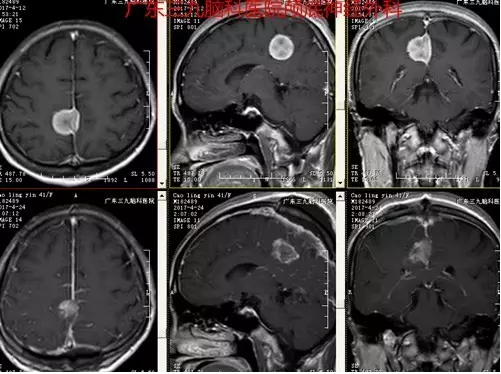

曹某,女性,41岁,因“头痛1月余”前来就诊。入院后完善相关检查,磁共振检查结果提示右侧额顶叶占位性病变,行“右侧大脑镰旁脑膜瘤切除术”,手术顺利,术后磁共振提示肿瘤切除。术后诊断:右侧大脑镰旁脑膜瘤。

图2: MR示右侧中央区大脑镰旁类圆形病变,强化明显

图4:术前术后MR增强对比,提示肿瘤全切除

据神经外一科刘振业主任介绍,大脑镰旁脑膜瘤是指基底附着于大脑镰或上矢状窦窦腔脑膜瘤,约占颅内脑膜瘤的11%-13%。手术治疗是大脑镰旁脑膜瘤的首选治疗方式。然而,由于镰旁脑膜瘤常常隐藏于大脑皮质下方,并且缺乏早期神经系统症状,导致早期诊断较为困难,一经发现往往肿瘤体积已形成占位效应,并引起如头痛、肢体麻木等神经症状。本例患者为中年女性,以头痛为首发症状,CT示小团状稍高密度影,边界欠清晰,密度尚均匀,血供丰富,MR见病变明显强化,脑膜尾征明显,邻近组织少许片状水肿。

由于肿瘤位置较深,且易侵犯静脉窦及重要的桥静脉,在上方有上矢状窦以及上引流静脉,而在下方则有胼缘动脉、胼周以及下矢状窦,能够进行手术的空间过于狭窄,在显露肿瘤方面存在困难。随着显微手术的发展,能够有效提高镰旁脑膜瘤的全切除效率,本例患者术中采用显微操作,手术时间短,术后复查MR达到I级全切,术后患者未见明确并发症,恢复良好出院。